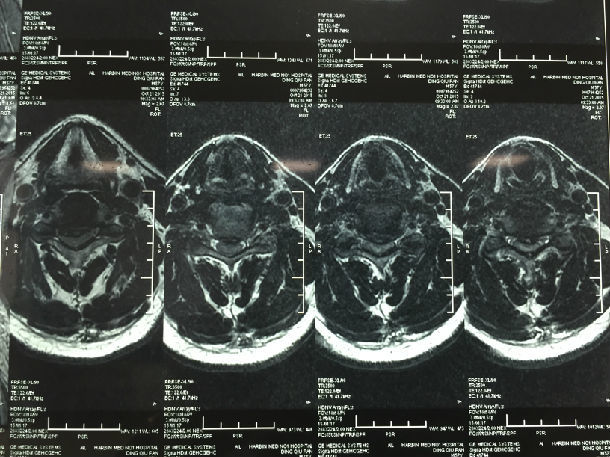

手术前-多节段颈椎间盘突出/黄韧带肥厚/颈椎管狭窄-脊髓损伤

手术前-颈髓明显受压伴脊髓损伤

显微镜下微创手术后-颈椎管明显增宽/脊髓受压解除/患者症状迅速好转